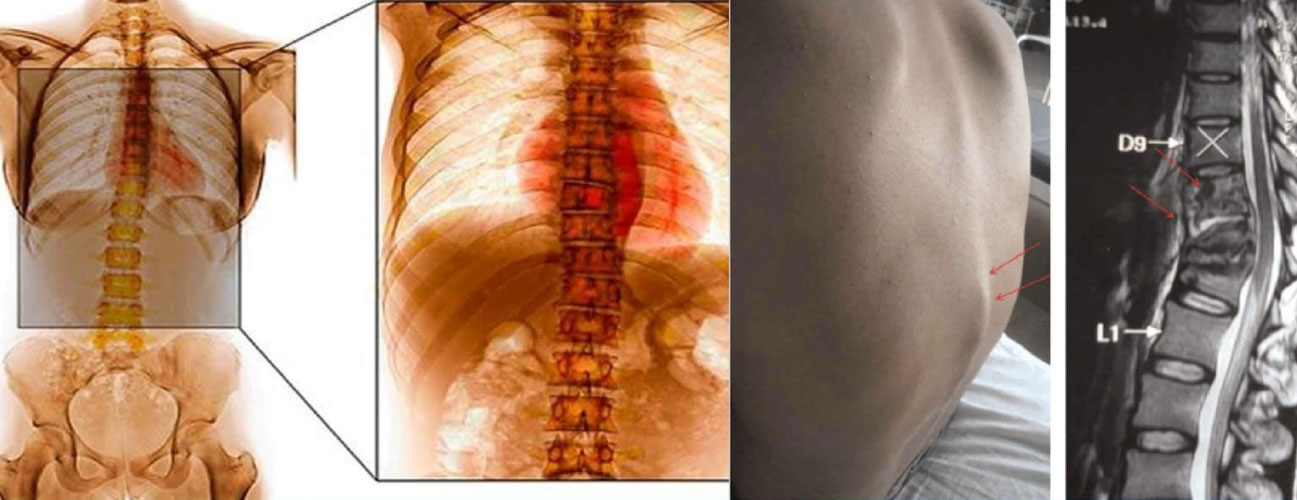

Spinal tuberculosis, also known as Pott's disease or tuberculous spondylitis, is a rare but serious form of tuberculosis that affects the spine. It occurs when the bacteria Mycobacterium tuberculosis infects the vertebral bones and intervertebral discs of the spine. Spinal tuberculosis can lead to severe spinal deformities, neurological deficits, and other complications if not treated promptly and appropriately. Here's an overview of spinal tuberculosis: